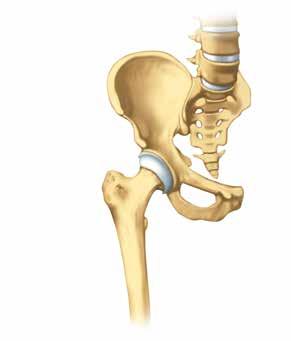

Gelenkersatz

Hat die Arthrose ein Gelenk bereits stark zerstört, kann das Einsetzen einer Prothese helfen, Betroffenen verloren gegangene Lebensqualität wiederzugeben. Schmerzen und Bewegungseinschränkungen können gelindert und oft sogar ganz zum Verschwinden gebracht werden. Selbständigkeit wird wieder möglich.

Der Fachbegriff für ein künst liches Gelenk lautet «Endopro these», abgeleitet von der grie chischen Vorsilbe Endo «innen». Endoprothese bedeutet also, dass ein künstliches Ersatzteil ins Körperinnere eingesetzt wird und dort für lange Zeit verbleibt.

Die am häufigsten eingesetzten Endoprothesen sind die der Hüft-, Knie- und Schultergelenke.

In vielen Spitälern gehören sie inzwischen zu den Standardoperationen. Ein künstliches Gelenk besteht aus mehreren Teilen: